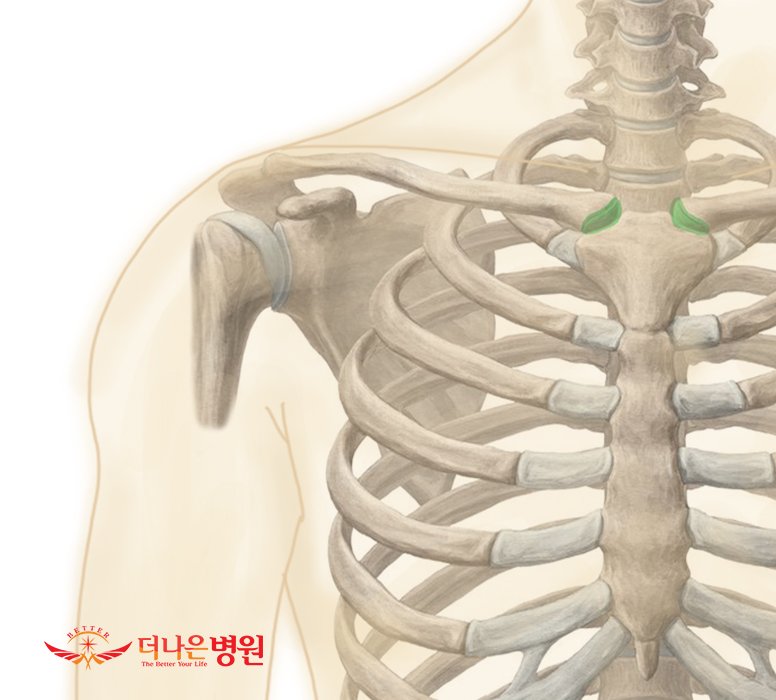

어깨관절복합체 내에 있는 4개의 관절

1. 흉쇄관절

2. 견쇄관절

3. 견흉관절

4. 관절와상완관절

어깨의 움직임을 일으키는 관절은 흉골과 쇄골이 이루는 흉쇄관절(Sterno-Clavicular joint), 견갑골의 견봉과 쇄골이 이루는 견쇄관절(Acromio-Clavicular joint), 견갑골과 흉부가 이루는 가관절(Pseudo-articular joint)인 견흉관절(Scapulo-Thoracic joint), 마지막으로 상완골과 견갑골의 관절와가 이루는 관절와상완관절(Gleno-Humeral joint)로 이루어 집니다. 견봉하관절(Subarcromial joint)을 포함하는 경우에는 5가지로 분류되기도 합니다. 어깨의 움직임은 이러한 관절들의 움직임으로 인해 인체에서 제일 자유롭고 다양하게 움직일 수 있습니다. 각각의 관절에서 정상적인 움직임이 이루어지지 않는다면 어깨의 움직임은 감소하게 되고 이는 어깨질환으로 이어지게 됩니다. 각 관절의 움직임과 주변 근육의 작용을 정확히 이해하고 운동과 재활을 하시면 건강한 몸을 유지하는 데 도움이 됩니다.